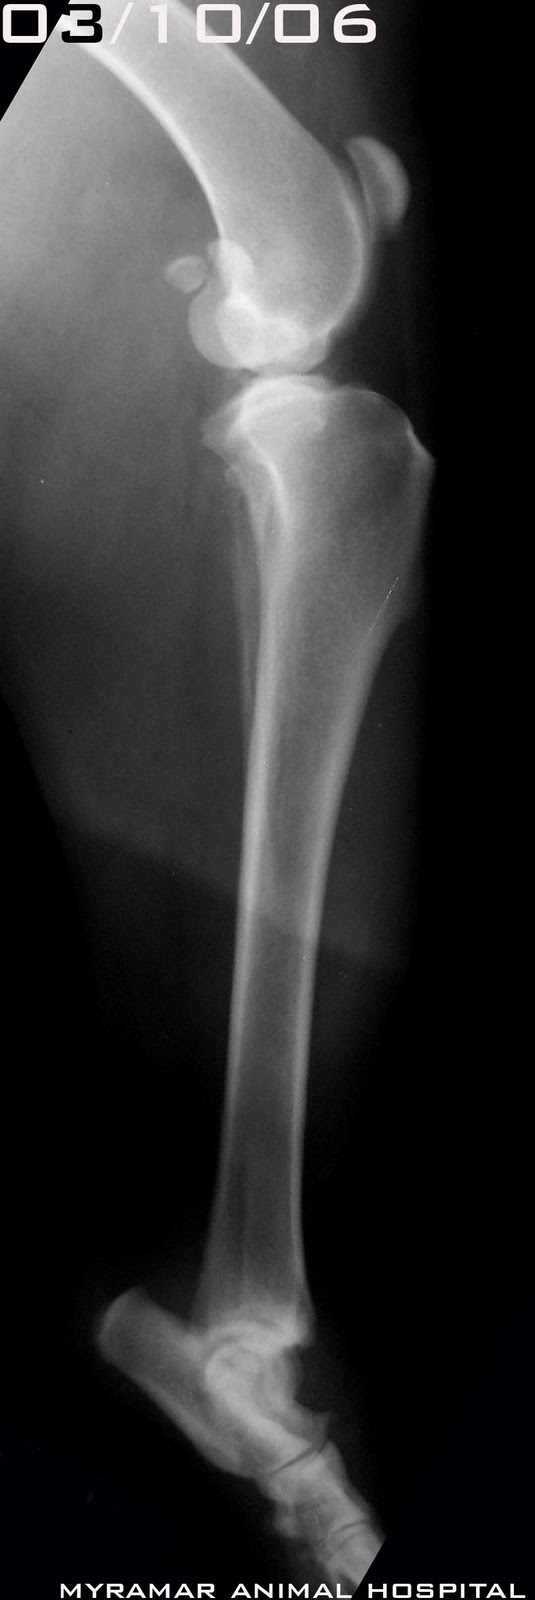

Fractura de los cuatro metatarsianos derechos

Los metatarsianos se estabilizan utilizando pines intramedulares del 1.8mm

Se presenta evolución radiográfica del caso